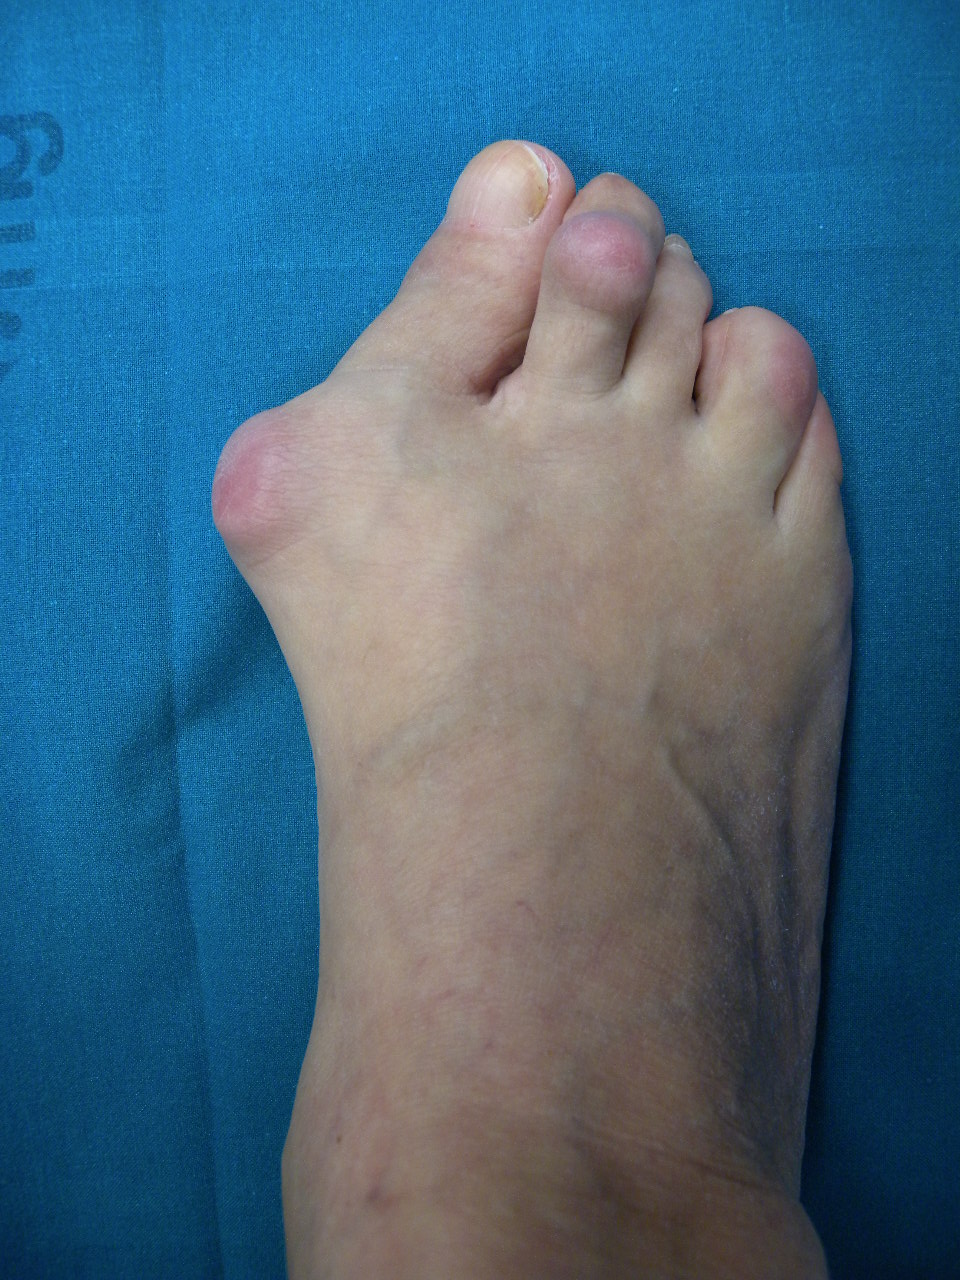

Tipicamente l’esordio è caratterizzato da dolori articolari accompagnati da tumefazione e rigidità che interessano le articolazioni di mani e piedi in maniera simmetrica ed aggiuntiva (cioè interessamento di altre articolazioni senza regressione nelle sedi già colpite). A livello del piede le articolazioni più frequentemente interessate sono le metatarso-falangee cioè le articolazioni alla base delle dita che vanno spesso incontro a lussazione patologica ; con minor frequenza sono interessate le articolazioni del retropiede e della caviglia (tra astragalo e scafoide , tra astragalo e calcagno, tibiotarsica). Se non adeguatamente trattata compaiono ipertrofia sinoviale ed erosioni dei capi articolari che comportano caratteristiche deformità ; in particolare all’avampiede si realizza spesso deformità in valgismo (cioè verso l’esterno) dell’alluce e delle dita laterali. Al retropiede il problema più comune è la comparsa di un progressivo piattismo che può arrivare a situazioni molto gravi per instabilità delle articolazioni interessati e per progressivo cedimento delle strutture tendinee , in particolare del tibiale posteriore.